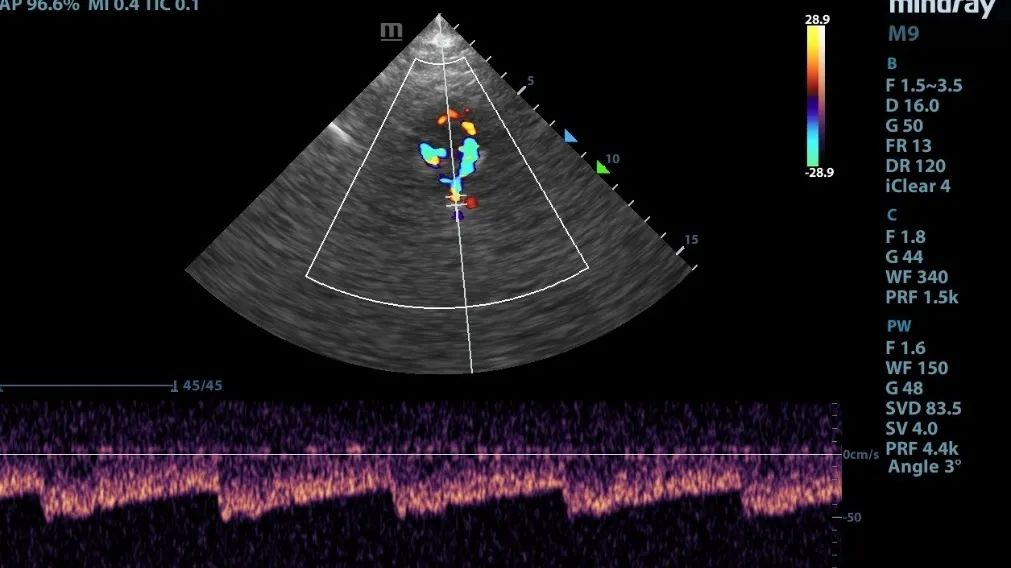

但是,TCCD就不一样了,它在TCD的基础上多了个彩色,也就是我们可以直观地看到颅内Villis环的彩色血流的走行及方向,因此就可以弥补TCD在使用上的一些不足。

TCCD图像能够显示大血管的走行及方向,更真实的反应血流速度

1.彩色显示血流充盈程度,可以显示狭窄处,狭窄前、狭窄后的血流动力学变化。

4.通过角度校正可以测出更真实的流速,TCD因为无法做到这点,流速往往容易高估。